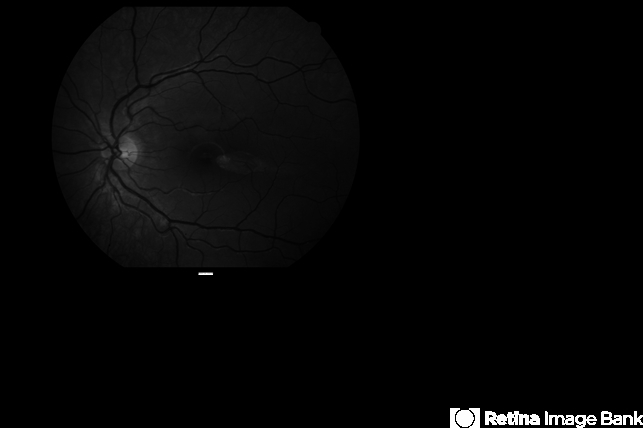

By Ian C Reddie, LLB (QUT), MBBS (Qld), FRANZCO, FASRS

- Fundus camera

- Red free picture of asymptomatic 8-year-old girl with incidental retinal finding at posterior pole of left eye.